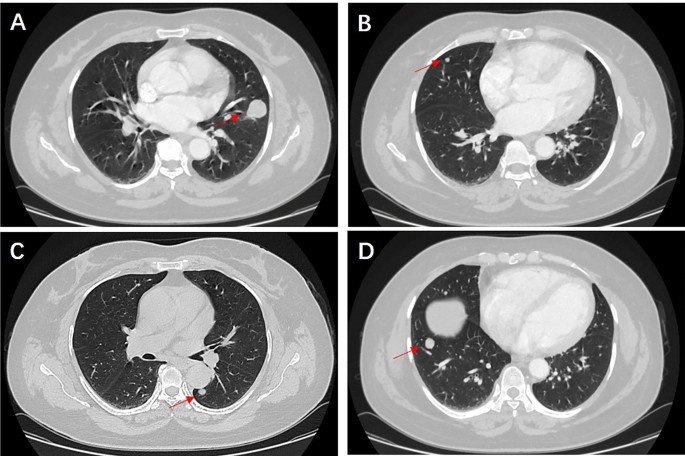

Figure 4 demonstrates that multiple PSP is not image specific; hence, multiple PSP diagnosis by a CT examination of the chest alone is difficult. Some patients with a previous history of malignant tumors might first consider the diagnosis of pulmonary metastases when they find multiple round nodules in the lungs. They may give up treatment at this time, but some reports6,7,8 suggest that multiple PSP can be diagnosed by puncture or surgical biopsy. Patients with multiple pulmonary nodules, who seek medical attention due to fever, can be misdiagnosed to have pulmonary tuberculosis by inexperienced doctors. Even if their tuberculosis-related tests are negative, they might still receive unnecessary anti-tuberculosis treatment5,9. However, some reports21 imply that patients with multiple PSP complicated with pulmonary tuberculosis may also exist. For patients who have multiple round pulmonary nodules with a previous history of malignant tumors, the time of discovery of pulmonary nodules is important. Similar to most scholars’ reports14,15,16, the diagnosis of multiple PSP is mainly based on the pathological diagnosis of postoperative resected specimens. The accuracy rate of percutaneous lung biopsy pathology and intraoperative rapid pathology diagnosis is low. Therefore, for multiple round pulmonary nodules which are difficult to be diagnosed, the authors propose to promptly perform a minimally invasive surgery for nodule resection and pathological diagnosis.

Chest CT of multiple PSP. This is a rare case of multiple PSP. The patient’s physical examination revealed the presence of multiple nodules in both lungs. A chest CT scan confirmed the existence of a total of 4 circular pulmonary nodules, distributed as follows: 1 in the upper lobe of the right lung, 1 in the lower lobe of the right lung, 1 in the upper lobe of the left lung, and 1 in the lower lobe of the left lung. The largest nodule, measuring 26 mm in diameter, was surgically excised from the left upper lobe and subjected to pathological analysis, which confirmed the diagnosis of PSP. Consequently, the final diagnosis was determined to be multiple PSP, and the patient is currently undergoing follow-up care.